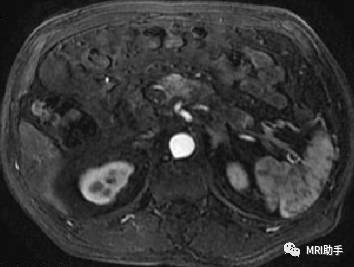

胰头肿块型慢性胰腺炎:胰体增粗,内见假囊肿和沿胰管走行的的多发钙化

②胰腺炎性肿块出现假性囊肿可能性较大,常可多发并超出胰腺轮廓。胰腺癌假囊肿发生率较低,体积较小,一般不超过胰腺轮廓。

④近端胰管及胆管的改变。不规则的胰管扩张或呈串珠状改变以炎性狭窄可能性大,CT还可见沿主胰管走行的钙化。而相对光滑均匀的扩张提示胰头癌恶性梗阻的可能性大。